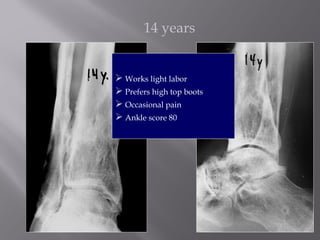

14 years

 Works light labor

 Prefers high top boots

 Occasional pain

 Ankle score 80